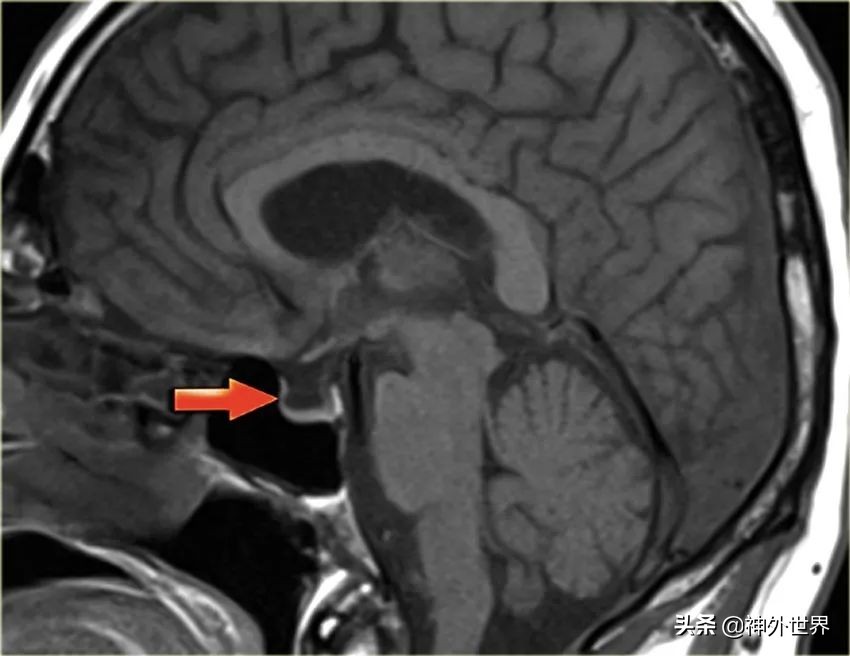

- 空泡蝶鞍(empty sella):蝶鞍内大部分为脑脊液信号,垂体背压到鞍底,压得很薄。【主要是由于鞍隔发育不良,导致脑脊液进入鞍内,只进不出,对垂体造成压迫,鞍内积存大量脑脊液,脑垂体受压变薄变小】。